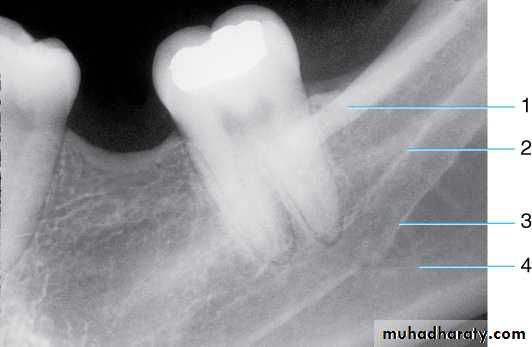

Radiograph of maxillary molar area. This radiograph shows (1) border (floor) of maxillary sinus, (2) maxillary sinus, (3) zygomatic process of maxilla, (4) zygoma, (5) lateral pterygoid plate, (6) lower border of zygomatic arch, (7) maxillary tuberosity, and (8) coronoid process of the mandible

Radiograph of maxillary molar area. This radiograph shows (1) hamulus (hamular process), which is a downward projection of the medial pterygoid plate, (2) lateral pterygoid plate, (3) coronoid process of the mandible, (4) maxillary tuberosity, and (5) maxillary sinus